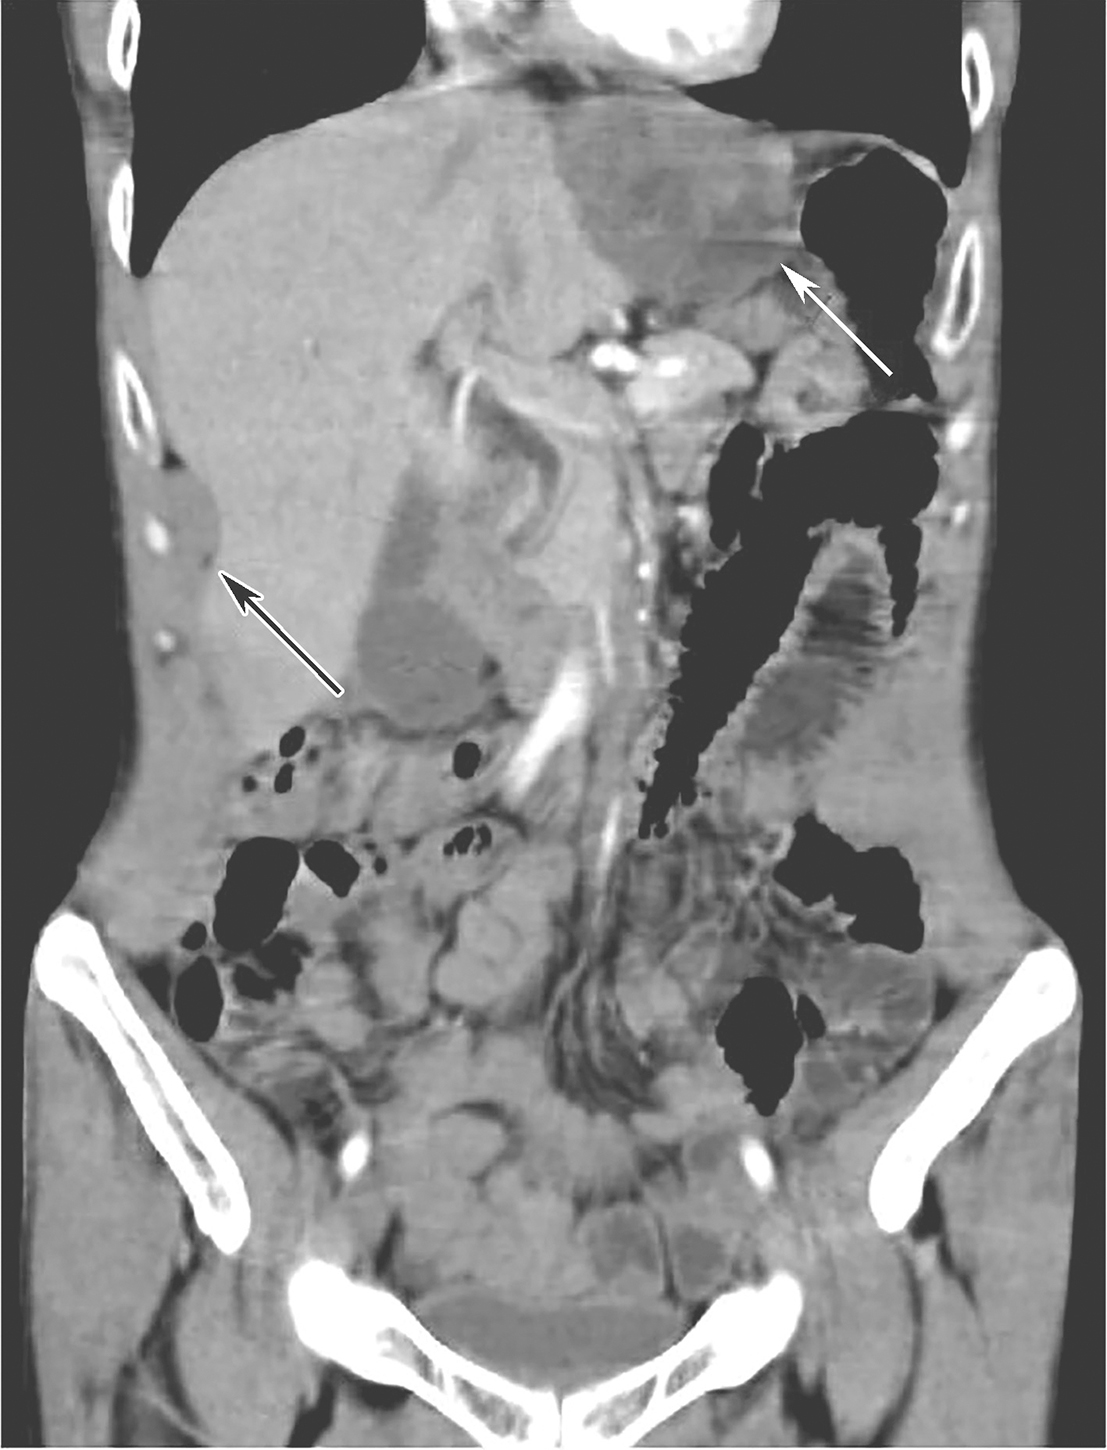

术后口服伊马替尼400mg/d辅助治疗30个月后(2015年11月18日),患者再次出现“吞咽阻塞感”,再次查腹部CT示:吻合口处可见新增团块状软组织肿物(51mm×49mm),增强后不均匀强化,考虑吻合口GIST复发。肝右前叶缘包膜新增软组织结节(36mm×20mm),腹腔新增软组织结节,考虑多发腹膜转移(图4)。行肝包膜下肿物穿刺基因检测:c-KIT外显子11缺失突变,c-KIT 外显子13点突变。

图4伊马替尼辅助治疗30个月后全腹增强CT(冠状位)

白色箭头示吻合复发病灶,黑色箭头示肝包膜转移灶